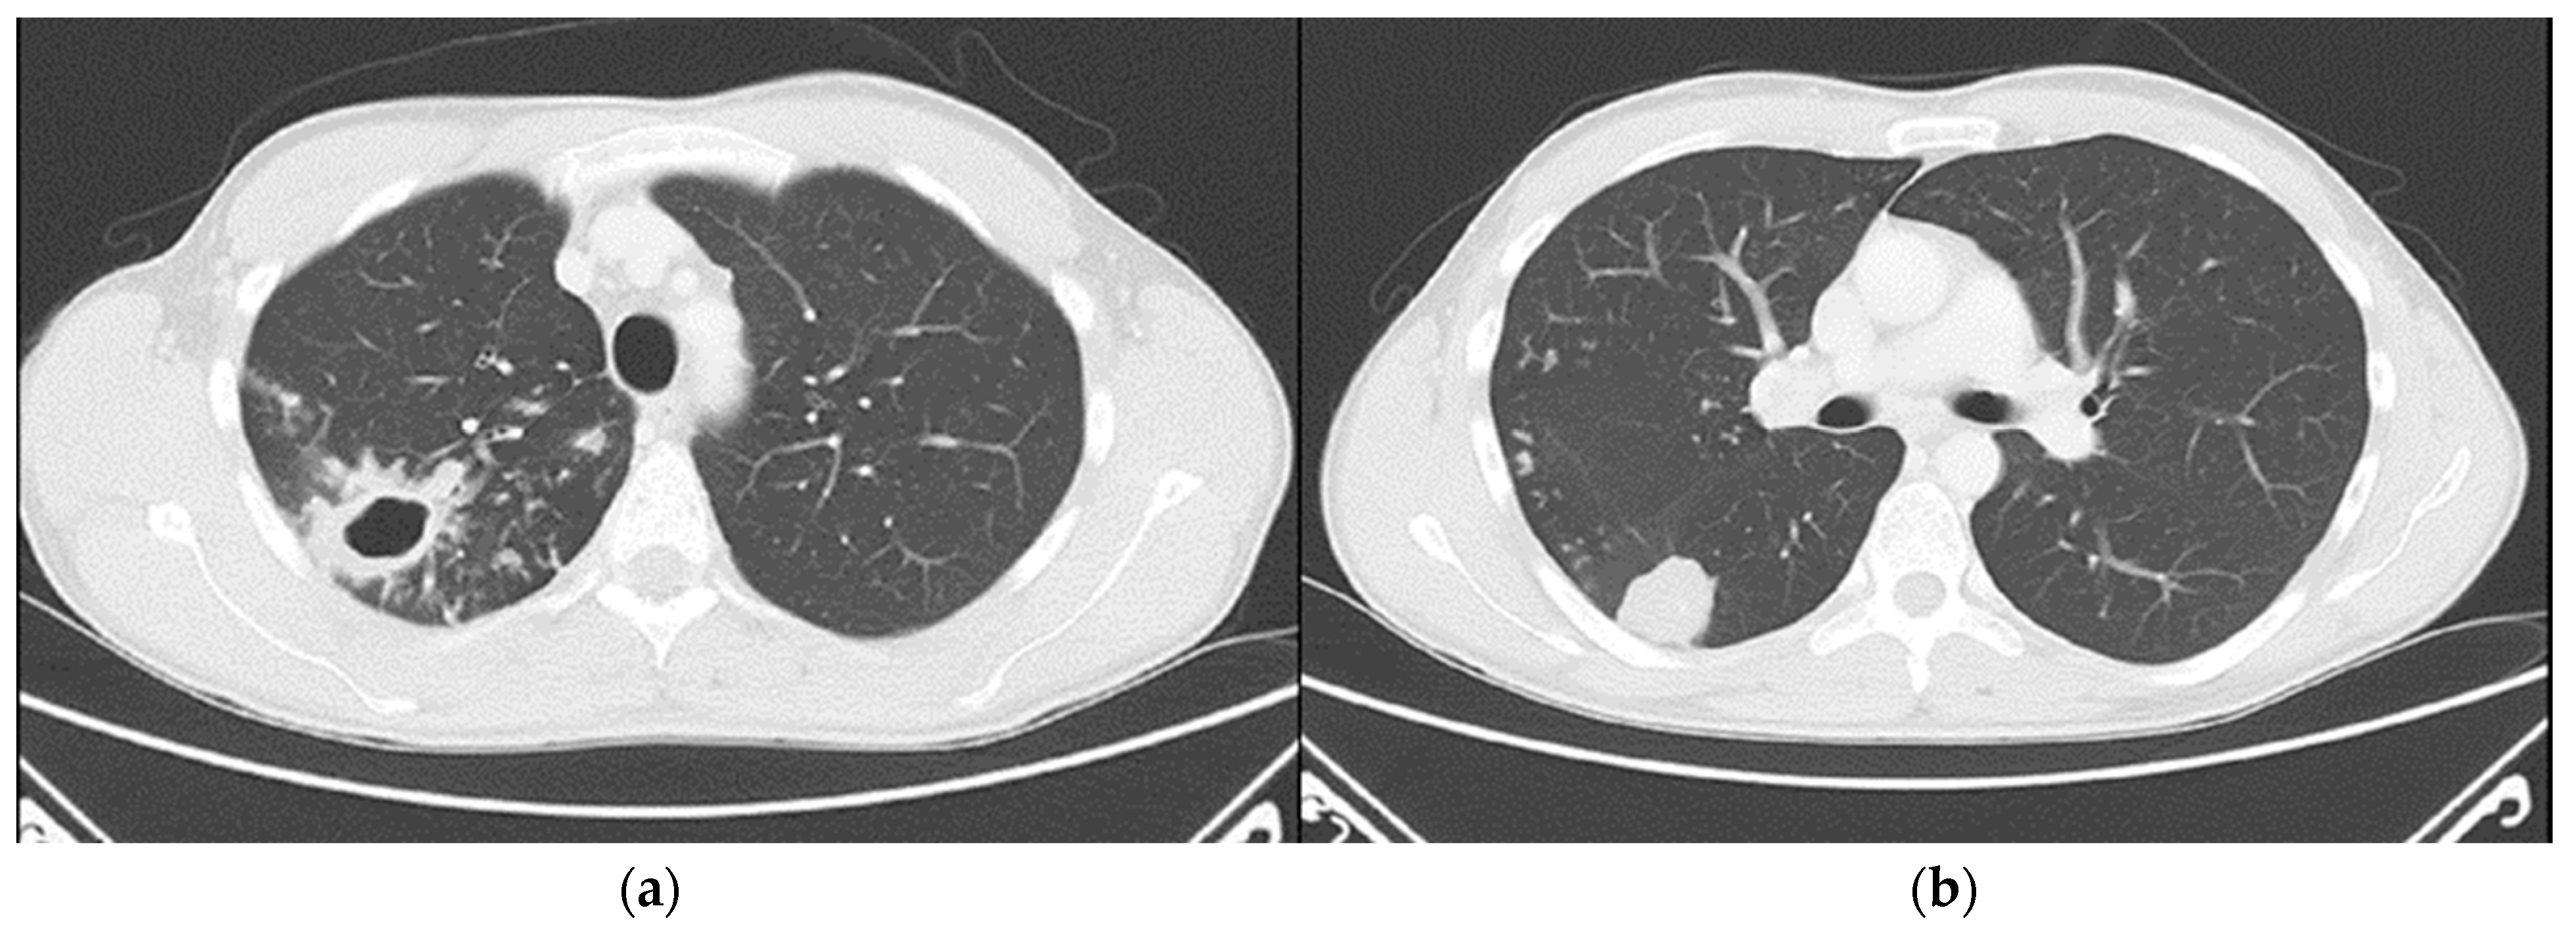

Chest computed tomography (CT) revealed numerous small confluent nodular lesions in the apical and posterior segments of the right upper lobe, forming a characteristic “tree-in-bud” pattern. These lesions ranged in size from a few millimeters to 2–3 cm and surrounded a cavitary lesion measuring up to 43 mm, adjacent to the pleura. A 3 cm nodular lesion with small calcifications was also observed in the upper segment of the right lower lobe, accompanied by a similar but less pronounced “tree-in-bud” pattern (Figure 2).

Figure 2. Chest CT scans (29 April 2024): (a) large cavitary lesion in the right upper lobe; (b) nodular lesion in the lower lung lobe and a discrete “tree-in-bud” pattern.